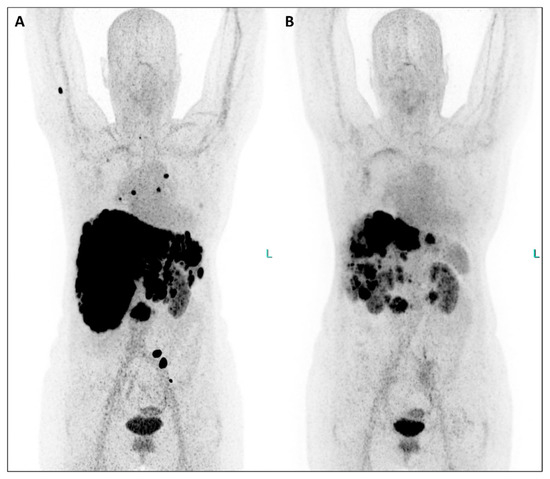

Figure 3. An extraordinary reduction in the uptake of the radiotherapeutic compound is evident in both the primary tumor and all metastatic lesions when comparing MIP images from post-therapeutic single-photon emission tomography/computed tomography (SPET/CT) (Figure 3, (A), July 2023; (B), September 2023; (C), November 2023). Furthermore, hepatomegaly is no longer present after therapy, and the bone lesions have completely disappeared. Equally significant, since the initiation of therapy, the patient has gained weight, experienced a notable reduction in abdominal pain, and seen improvement in her energy levels, enabling her to resume physical activity and engage in everyday life activities. Additionally, their serum biomarkers exhibited a substantial decrease throughout the TANDEM-PRRT courses: neuron-specific enolase decreased from 418 ng/mL before therapy to 25.8 ng/mL (a reduction of 93.8%), and Chromogranin A decreased from 2950 ng/mL to 270 ng/mL (a reduction of 90.8%).